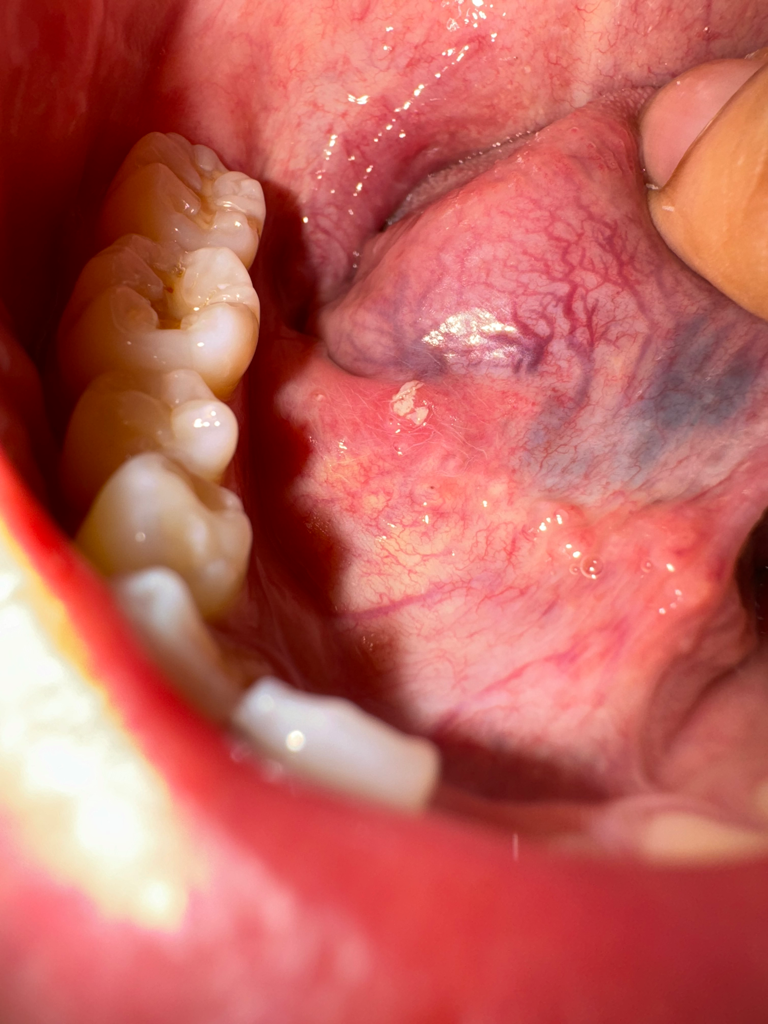

혀 밑에 통증이 자꾸 느껴져서 봤더니 흰색 염증이 있어요.

사진보시면 흰색 염증같은 거 있는 곳에 통증이 있어요.

동그라미 쳐놓은거는 알보칠바르기전이고 동그라미 없는거는 알보칠을 바른 후 입니다

• 4번 째 사진